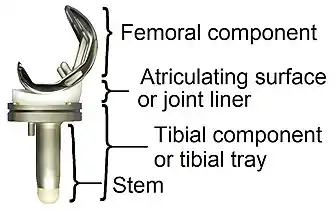

Components and zones

Standardized zones around the components are used for specifying for example signs of loosening on radiographic follow-up. There are various classification systems for specifying such zones,[42][43] including by KS (Knee Society) zones published in 2015.[41]

Main components of a knee prosthesis.

Main components of a knee prosthesis. KS zones, anteroposterior (AP) view.[41]

Specific KS zones are as follows, with * meaning that the zone can be specified as "A" (anterior), "P" (posterior), "M" (medial) or "L" (lateral):[41]

- Femoral component (lateral view)

- Zone 1 and 2: Anterior and posterior flange, respectively.

- Zone 3: Central box/distal fixation region, where "A" and "P" designate the respective chamfers if visible*

- Zone 4: Stem extension*

- Zone 5: Stem

- Tibial component:

- Zone 1: Anterior on lateral view, medial on anteroposterior (AP) view.

- Zone 2: Posterior on lateral view, lateral on AP view.

- Zone 3: Central keel/stem/peg fixation region*

- Zone 4: Stem extension*

- Zone 5: Inferior aspect of keel or stem